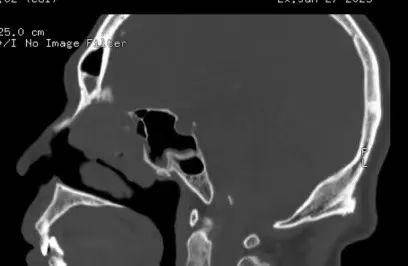

患者男,59岁,因左鼻腔涕中带血40余天入院,入院CT、MRI示前颅底肿瘤,侵犯前颅底骨质及硬脑膜。入院诊断:前颅底肿瘤。入院后在病房行活检示(左侧鼻腔)嗅神经母细胞瘤,排除手术禁忌症后行全麻下经鼻内镜下前颅底肿瘤及前颅底部分骨质磨除、硬脑膜切除,鼻颅底重建手术。

CT、MRI示前颅底肿瘤,侵犯前颅底骨质及硬脑膜